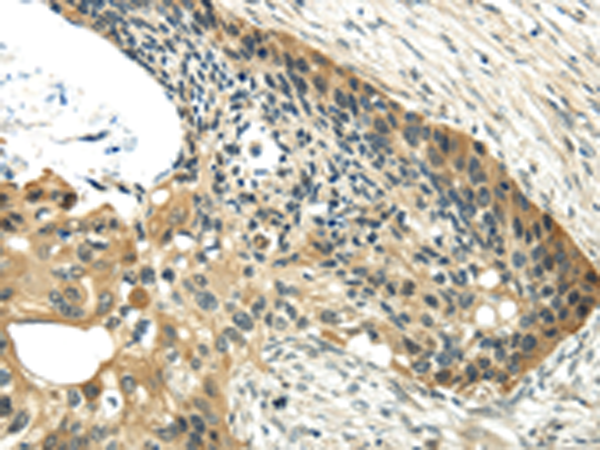

分类: 科研抗体货号: P08937别名:应用: IHC反应种属: Human